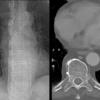

paraspinal lines